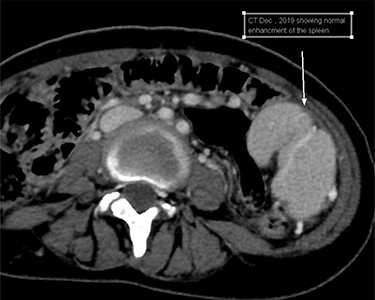

Patient was then pushed to the operating theater for diagnostic laparotomy and possible splenectomy. Abdomen was explored an 8-cm midline incision revealing a wondering spleen in the mid abdomen connected only with colonosplenic ligament with twisted splenic pedicle. Splenectomy performed and patient was shifted to postanesthesia care unit in stable condition (Fig. 3). Hospital course was unremarkable and patient was kept in the hospital for three days for observation then discharged home.

Intraoperative clinical photographs showing infarcted malformed WS.